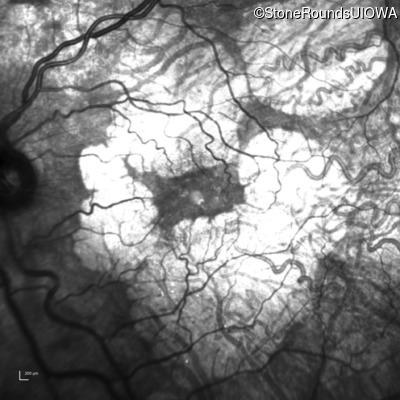

Infrared Fundus Photograph - Right - 20/40 -2

Exemplar